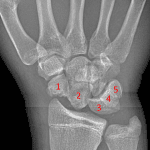

- Acute comminuted scaphoid waist fracture with midcarpal dislocation

- Overlying soft tissue swelling

Acute comminuted scaphoid waist fracture with midcarpal dislocation. Overlying soft tissue swelling.